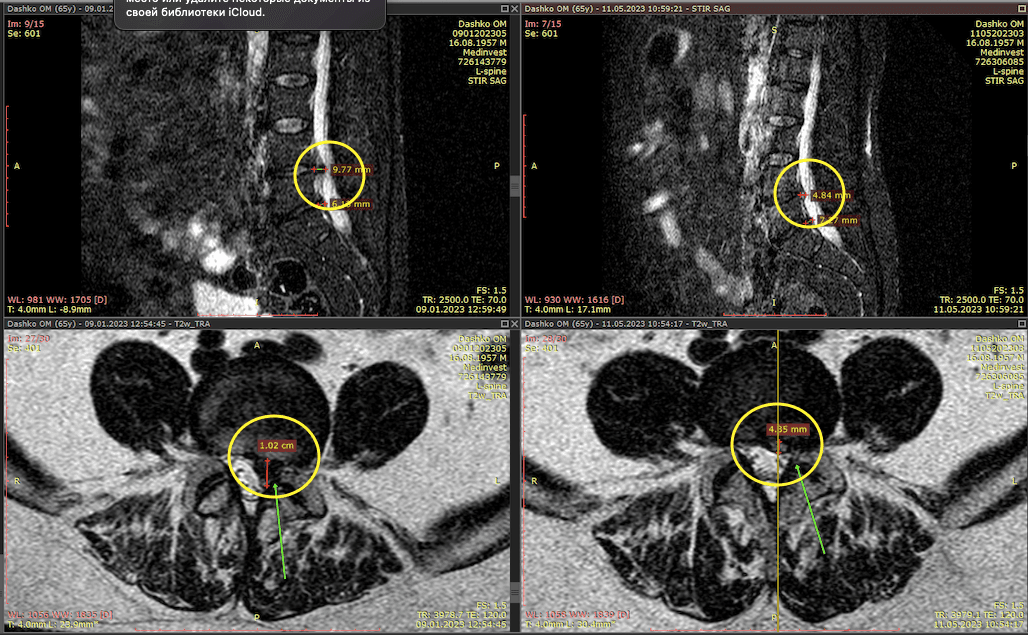

| МРТ | Шукає зміни в м’яких тканинах |